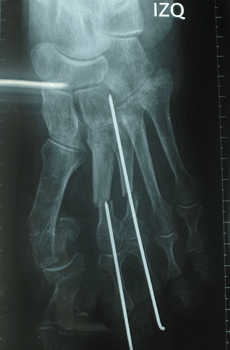

RESULTADOS

Caso 1: Hallux Valgus del Adulto